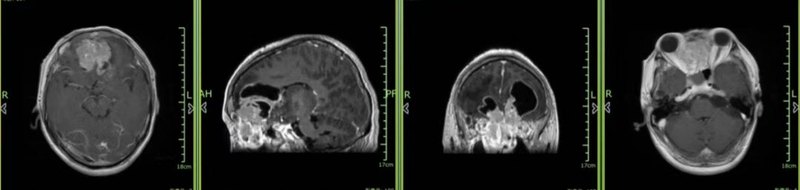

病史简介:患者,男性,58岁,因“嗅觉减退半年,头痛伴视物重影半月”入院。现病史:患者半年前出现嗅觉减退,未予治疗。半月前患者诉头痛,以前额及右眼眶处为主,为持续性胀痛,阵发性加重,维持0.5-1h后疼痛程度缓解,伴有视物重影,眼球内收活动受限,诉右颌下淋巴结肿大,浙大二院颅脑增强MRI提示:筛窦区-额叶囊实性占位,考虑恶性肿瘤(嗅神经母细胞瘤首先考虑)(图1)。浙大二院耳鼻喉科行鼻内镜取组织活检提示考虑嗅神经母细胞瘤,建议住院手术治疗。为求进一步诊断治疗,于浙大四院就诊,门诊拟诊为“前颅底占位性病变:嗅神经母细胞瘤可能”收住入院。 既往史:左侧淋巴结切除术后20年余,术后病理提示良性。否认高血压、糖尿病等病史。 入院查体:神清,语利,双侧颌下各可触及1枚直径约2cm肿物,质地硬,无压痛,活动度一般,双侧视力、视野粗测可,瞳孔等大正圆,直径3:3mm,对光反射灵敏,双眼球内收略受限,其余方向运动充分,眼裂对称;面部无感觉异常、减退,额纹存在,面纹对称,口角无歪斜,伸舌居中,双侧听力粗测无减退,嗅觉粗测明显减退,四肢肌力v级,深浅感觉存在,肌张力对称,巴氏征未引出。图1 颅脑MRI增强检查:筛窦区-额叶见团块状囊实性异常信号影,占位效应重,病灶左右向两侧眼眶突。上下呈跨颅窝改变,呈“哑铃”状,边界尚清,形态不规则,范围约74×49×72mm。 诊治经过:入院后完善术前,视野检查提示散在视野缺损(图2)。综合上述检查结果,诊断考虑:前颅底-筛窦占位性病变,嗅神经母细胞瘤考虑。术前经科室讨论,考虑使用单一手术入路难以全切肿瘤,与家属充分沟通后决定行经鼻内镜联合冠状切口的额底入路切除嗅神经母细胞瘤。 图2 视野检查手术经过如下:(1) 鼻腔部分:神经内镜下切除右侧中鼻甲,离断鼻中隔,暴露蝶窦前壁和双侧蝶窦开口,磨除蝶窦前壁后进入蝶窦。然后由后方逐渐向前方暴露前颅底,开放双侧筛窦,可见肿瘤组织伴增生骨质,肿瘤呈灰红色,质地较韧,血供丰富,取少量肿瘤组织送冰冻病理提示“(颅底肿瘤)小蓝细胞恶性肿瘤,嗅神经母细胞瘤首先考虑”。随后分块切除由前颅底侵犯至鼻腔内的肿瘤组织,可见双侧筛前、筛后动脉参与肿瘤血供,予以离断,最后暴露颅底肿瘤。(2) 开颅部分:取冠状切口左侧单额入路,硬膜外悬吊后弧形剪开硬膜,抬起额叶,暴露肿瘤组织,见肿瘤广泛附着于前颅底。内镜下供血动脉离断后,颅内肿瘤血供明显减少。离断肿瘤基底,切开大脑镰,暴露对侧肿瘤组织。CUSA辅助下肿瘤内减容,然后小心分离肿瘤与额叶粘连,分块切除,注意保护后方的大脑前动脉复合体、两侧视神经和颈内动脉。显微镜下肿瘤基本切除,与鼻腔彻底打通。但肿瘤基底处较深,仍有少许肿瘤残留,取30度内镜下从颅内探查瘤腔,彻底切除位于前方颅底内侧面和嗅沟周围少量残余肿瘤。(3) 颅底重建:显微镜下,取带蒂骨膜瓣,附着于前颅底缺损处,取大腿脂肪填塞固定骨膜瓣,外覆免缝人工脑膜,生物胶水胶封。取大腿阔筋膜,于鼻内镜下覆盖于颅底硬膜缺损处,生物胶水固定,碘仿纱条填塞支撑。手术过程顺利,术后送ICU常规护理,予以抗感染、预防癫痫、护胃、雾化吸痰等对症治疗,术后患者生命体征平稳。术后复查CT未见明显出血(图3)。颅脑MRI增强检查提示肿瘤彻底切除,邻近脑实质未见明显水肿出血(图4)。常规病理检查提示:(1.颅底肿瘤 冰冻及常规)嗅神经母沺胞瘤(Hyams分级4级)。 图3 颅骨CT扫描+三维重建检查:颅脑、筛窦术后改变,未见明显出血。图4 颅脑MRI增强检查:前颅底、筛窦术后改变,未见明显水肿出血。 讨论:嗅神经母细胞瘤(olfactoryneuroblastoma,ONB)一种罕见的来源于特化的感觉性嗅神经上皮的恶性神经外胚层肿瘤,仅占所有鼻肿瘤的3%~5%,于1924年首次报道并命名,发病率约为0.4/100万[1]。这类肿瘤好发于鼻腔顶部、筛板区,可向鼻窦、眼眶、前颅底侵袭生长[2]。嗅神经母细胞瘤的临床表现由解剖位置决定,早期病灶较小时无明显症状,常导致诊断延迟,就诊时多属于中晚期,随病灶增大、病情进展,临床症状表现为鼻塞、反复鼻出血、嗅觉减退、头面部疼痛、视物模糊、眼球突出等,常为单侧症状[3]。嗅神经母细胞瘤的治疗方式主要包括手术、放疗和化疗,首选治疗方法为完整、彻底的外科手术切除,并联合放疗。对于高级别的ONB患者,完全切除后的辅助化疗也是有益的[4]。由于嗅神经母细胞瘤出现在上鼻腔和前颅窝之间的交界处的解剖位置,临床手术治疗存在一定的挑战,手术的最佳时机、最佳方法以及计划切除的范围必须与术后神经功能障碍的风险以及预防其他并发症(脑积水、脑脊液漏、颅内感染)的需要相结合。过去几十年治疗手段一直在不断改进,生存率也得以改善。最初采用经面部入路切除肿瘤,而部分浸润脑膜层进入大脑的肿瘤,通常需要两次手术或者颅面联合入路,实现肿瘤的整块切除[5]。另一方面,内镜手术技术不断发展,与经面、经颅入路相比,内镜手术的优点是手术时间较短、无外部切口、脑实质损伤最小、不操作神经血管结构、无需输血。部分鼻旁和前颅底肿瘤可以使用内窥镜技术完全切除[6,7]。然而,传统鼻内镜手术在某些情况下应用有限,包括肿瘤侵犯眶周鞘、眼眶结构、前桌、额窦侧隐窝以及侵犯颅内>2cm的肿瘤;仅使用传统的内窥镜方式很难完全切除肿瘤[8, 9]。经颅+经鼻内镜联合入路治疗颅内病变是不错的组合术式。与单独入路相比,经颅+经鼻内镜联合入路的优势在于:在血供复杂的颅底肿瘤中能够更好的分离血管,控制出血;对肿瘤的切除更为彻底;能够更好的保留重要组织结构;可以进行非常牢靠的颅底重建;降低感染等并发症的风险。通常来说,累及额窦前壁、大范围硬膜,颈内动脉或者脑实质的颅底肿瘤不建议单独使用经鼻内镜入路。在这种情况下,为了提高肿瘤的可见度和切除程度,以及控制出血,可以增加经颅入路[10]。当然,这种联合入路还要考虑患者的手术史,解剖结构是否清晰等基础条件。根据术前影像结果,本例患者的肿瘤病变位于前颅底中线,向上下、两侧的侵犯范围较大,仅使用经额入路无法处理肿瘤侵犯筛窦的基底部分,且容易造成脑脊液漏和颅内感染,而单一经鼻内镜入路也无法处理颅内上方及两侧的肿瘤组织。因此主刀医生选择内镜下切除筛窦部分肿瘤,离断肿瘤血供,打通颅底。而后,经单额入路,暴露前颅底,切除颅内横向扩展生长的肿瘤。术后患者恢复良好,未发生脑脊液漏及感染等并发症。该手术方案结合了内镜及开颅显微镜下手术的优点,为处理鼻窦的肿瘤侵犯前颅底病变提供了新的经验。 参考文献[1] Olmo HR,StokesSM,FossRD.Olfactoryneuroblastoma:acasereport[J].Headandneckpathology,2016,10(2):256-260.[2] ZhangL, Niu K,ZhuK,etal.Long-termprognosticanalysisafterendoscopicendonasalsurgeryforolfactoryneuroblastoma:aretrospectivestudyof13cases[J]. PloS one,2016,11(11):e0166046.[3] 杨柳青,张义,张磊. 嗅神经母细胞瘤CT及MRI影像表现1例报道 [J]. 中国临床研究, 2023, 36 (06): 955-957.[4] YangJ,SongX,LaiY,etal.Developmentandvalidationofapostoperativenomogramforpredictingoverallsurvivalafterendoscopicsurgicalmanagementofolfactoryneuroblastoma[J]. EClinicalMedicine,2020,29.[5] Dulguerov P, Allal AS,CalcaterraTC. Esthesioneuroblastoma:ameta-analysisandreview[J].Thelancetoncology,2001,2(11):683-690.[6] Radulesco T, Penicaud M, Dessi P,etal.Endoscopicsurgeryfor sinonasal tumors:the transcribriform approach[J].JournalofStomatology,OralandMaxillofacialSurgery,2017,118(4):248-250.[7] YuY,El‐SayedIH,McDermottMW,etal.Duralrecurrenceamong esthesioneuroblastoma patientspresentingwithintracranialextension[J].TheLaryngoscope,2018,128(10):2226-2233.[8] SnydermanCH,PantH, Carrau RL,etal.Whatarethelimitsofendoscopicsinussurgery?:theexpandedendonasalapproachtotheskullbase[J].TheKeiojournalofmedicine,2009,58(3):152-160.[9] TanakaK,OzakiT.NewTNMclassification(AJCCeighthedition)ofboneandsofttissuesarcomas:JCOGBoneandSoftTissueTumorStudyGroup[J].Japanesejournalofclinicaloncology,2019,49(2):103-107.[10] VanNgoC,NguyenH, Aklinski J,etal.Combinednasalendoscopicand subfrontal craniotomyforresectiontumorsofanteriorskullbase[J].JournalofCraniofacialSurgery,2022,33(2):588-591.